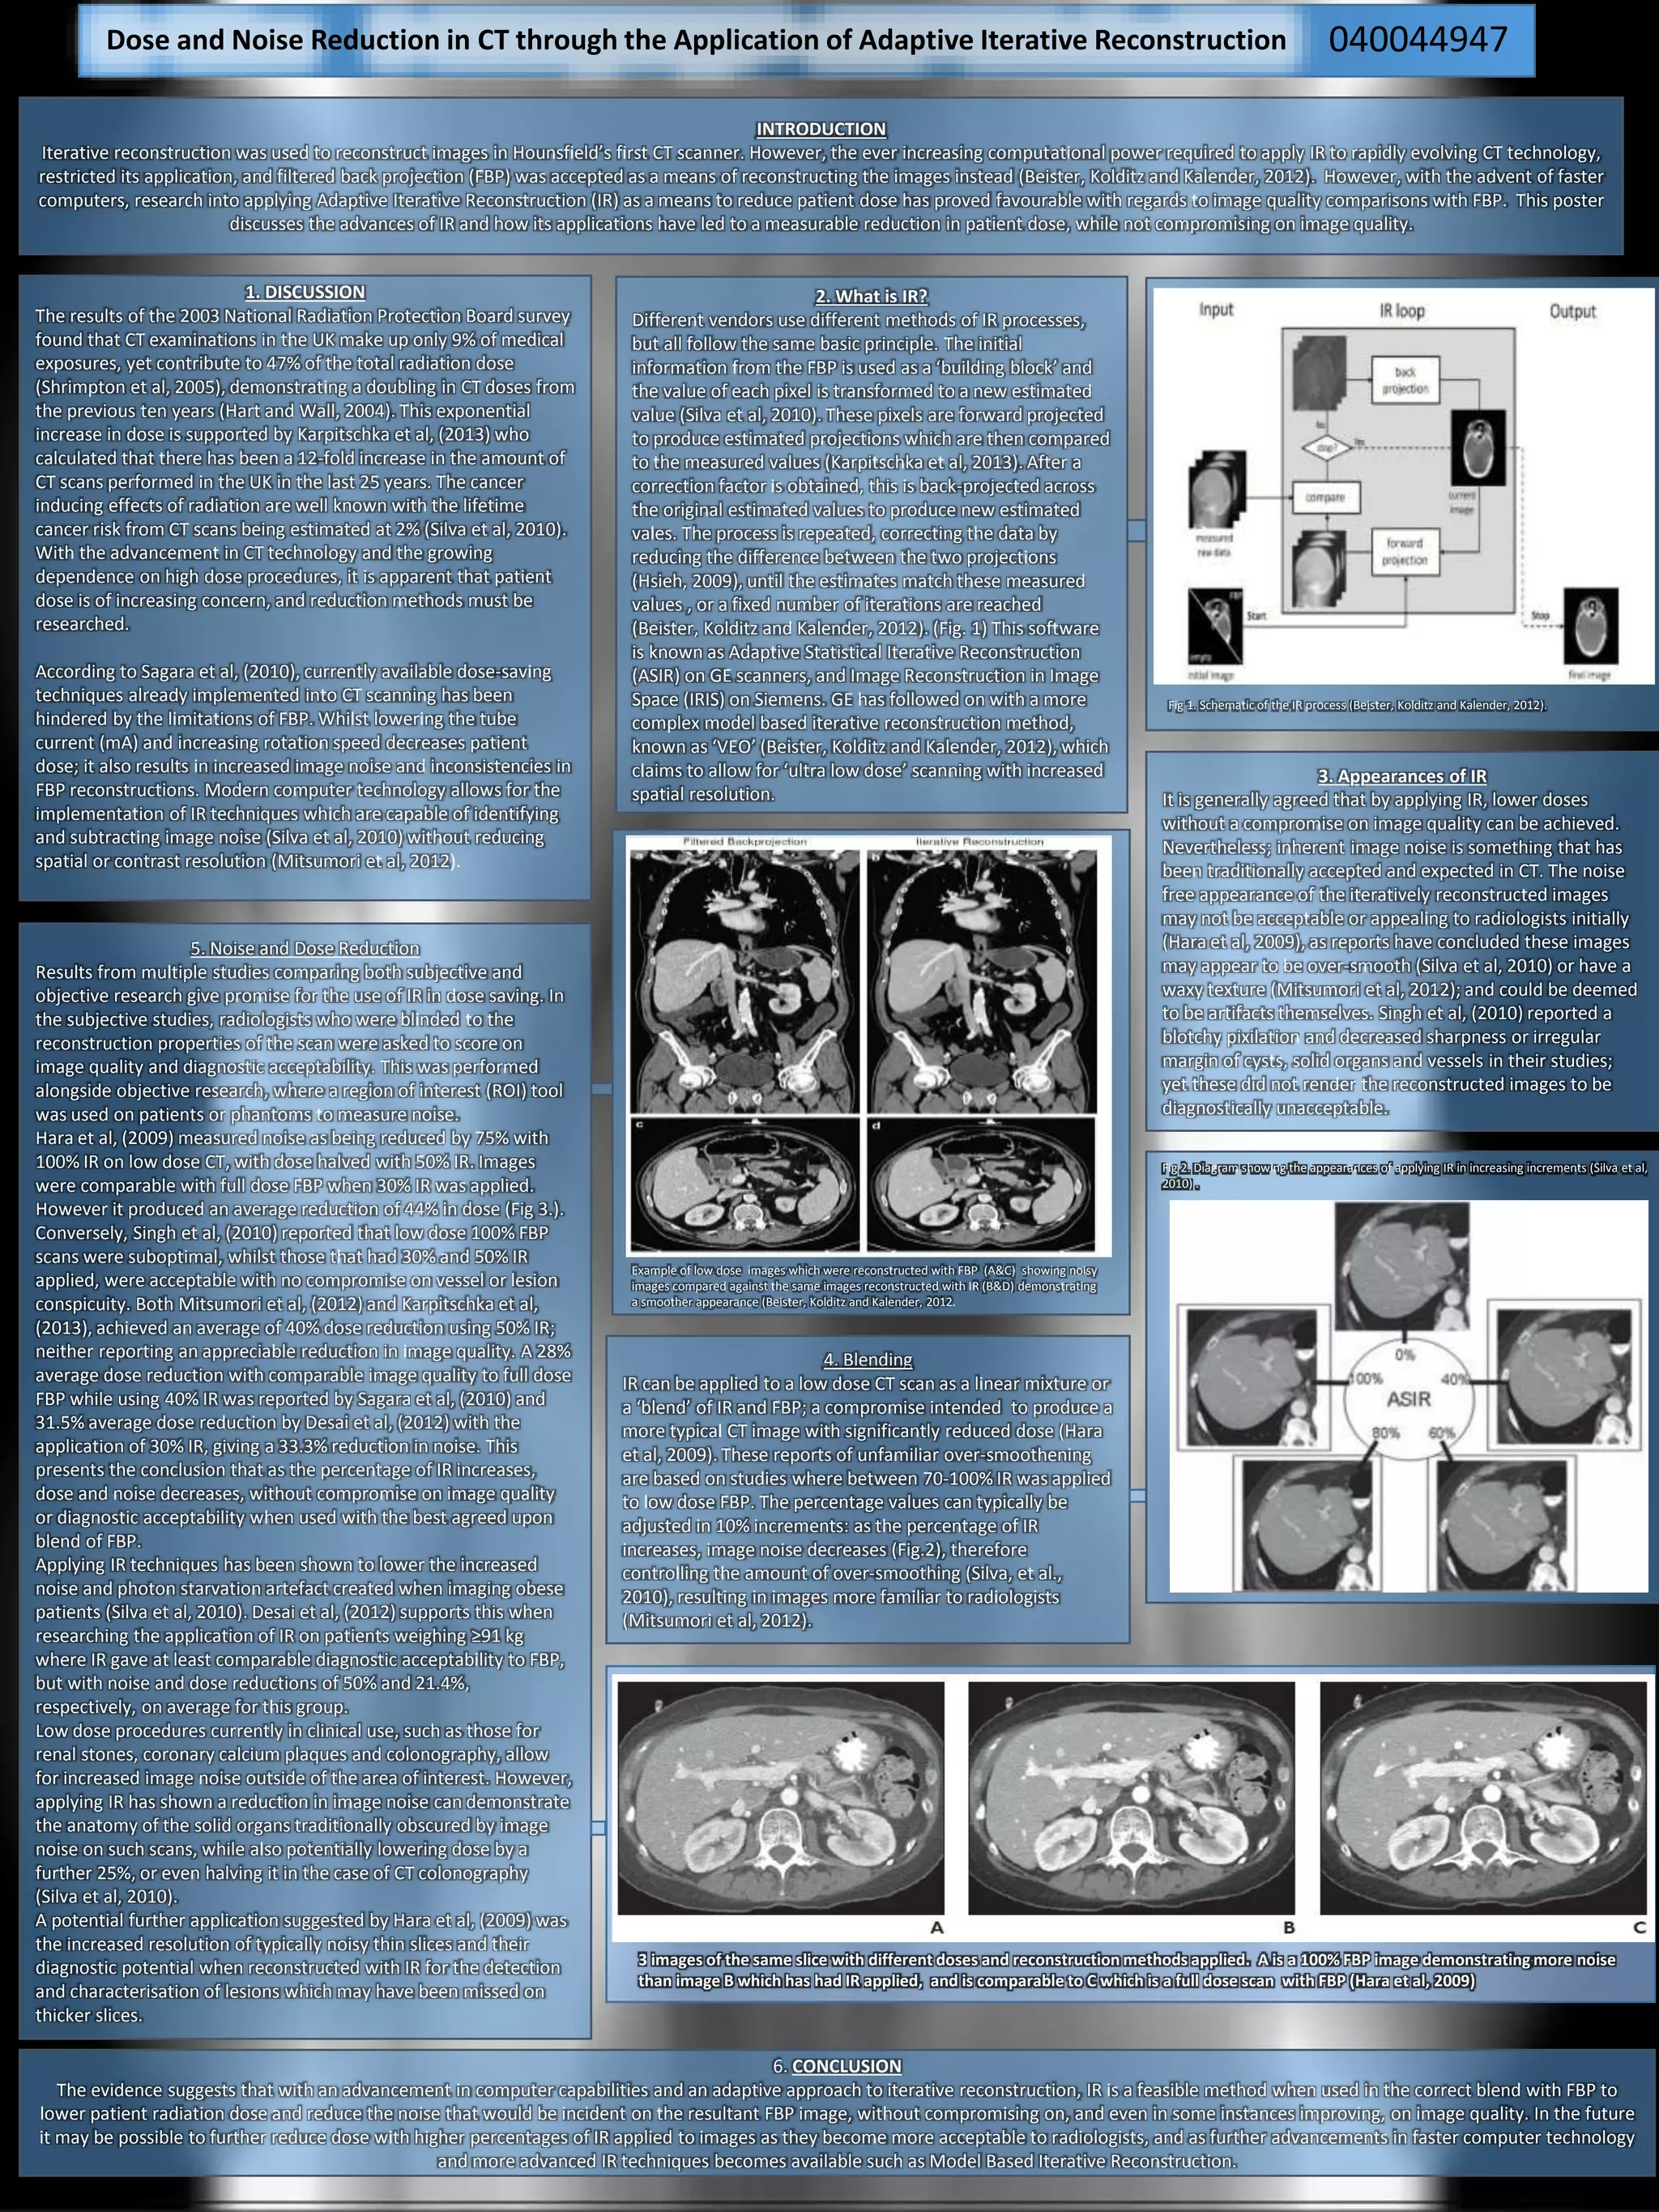

3 images of the same slice with different doses and reconstruction methods applied. A is a 100% FBP image demonstrating more noise

than image B which has had IR applied, and is comparable to C which is a full dose scan with FBP (Hara et al, 2009)

Hara et al, (2009) measured noise as being reduced by 75% with

100% IR on low dose CT, with dose halved with 50% IR. Images

were comparable with full dose FBP when 30% IR was applied.

However it produced an average reduction of 44% in dose (Fig 3.).